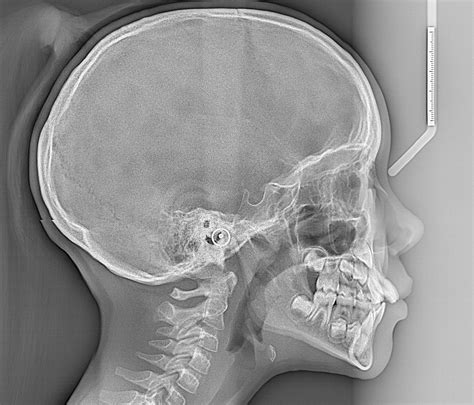

A Cephalometric X Ray is a specialized type of radiograph used to analyze the relationship between the teeth and the jaw. It provides a two-dimensional view of the skull, focusing on the facial bones and teeth. This imaging technique is invaluable for diagnosing and treating various orthodontic conditions, including malocclusions, jaw discrepancies, and facial asymmetries.

The patient’s head is positioned so that the Frankfort plane (a line drawn from the top of the ear canal to the bottom of the eye socket) is parallel to the floor. This ensures that the X-ray beam passes through the skull at the correct angle, providing an accurate image of the facial bones and teeth.

The X-ray machine is then activated, and a beam of radiation is directed through the patient’s head. The radiation passes through the soft tissues and is absorbed by the denser bone structures, creating a detailed image on the X-ray film or digital sensor.

Interpreting a Cephalometric X Ray requires a thorough understanding of craniofacial anatomy and orthodontic principles. The orthodontist analyzes various landmarks and measurements to assess the patient’s dental and skeletal relationships. Some of the key landmarks and measurements include:

Key Landmarks

The following table outlines some of the key landmarks used in Cephalometric X Ray analysis:

Landmark Description

Sella (S) The center of the sella turcica, a depression in the sphenoid bone

Nasion (N) The most anterior point of the frontal bone at the nasofrontal suture

Orbitale (Or) The lowest point on the inferior margin of the orbit

Pogonion (Pog) The most anterior point on the chin

Gnathion (Gn) The most inferior point on the symphysis menti